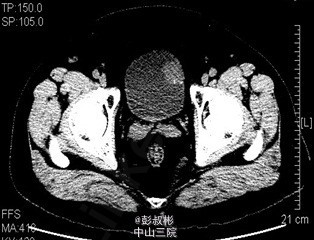

膀胱肿瘤电切实录--看看膀胱癌长这样

主诉 病史

68岁,男性,反复肉眼血尿3个月。盆腔CT:膀胱左前下侧壁约20×21×21 mm肿块,考虑膀胱癌可能性大。术前诊断:膀胱癌。患者合并心肺功能不全,要求保留膀胱。